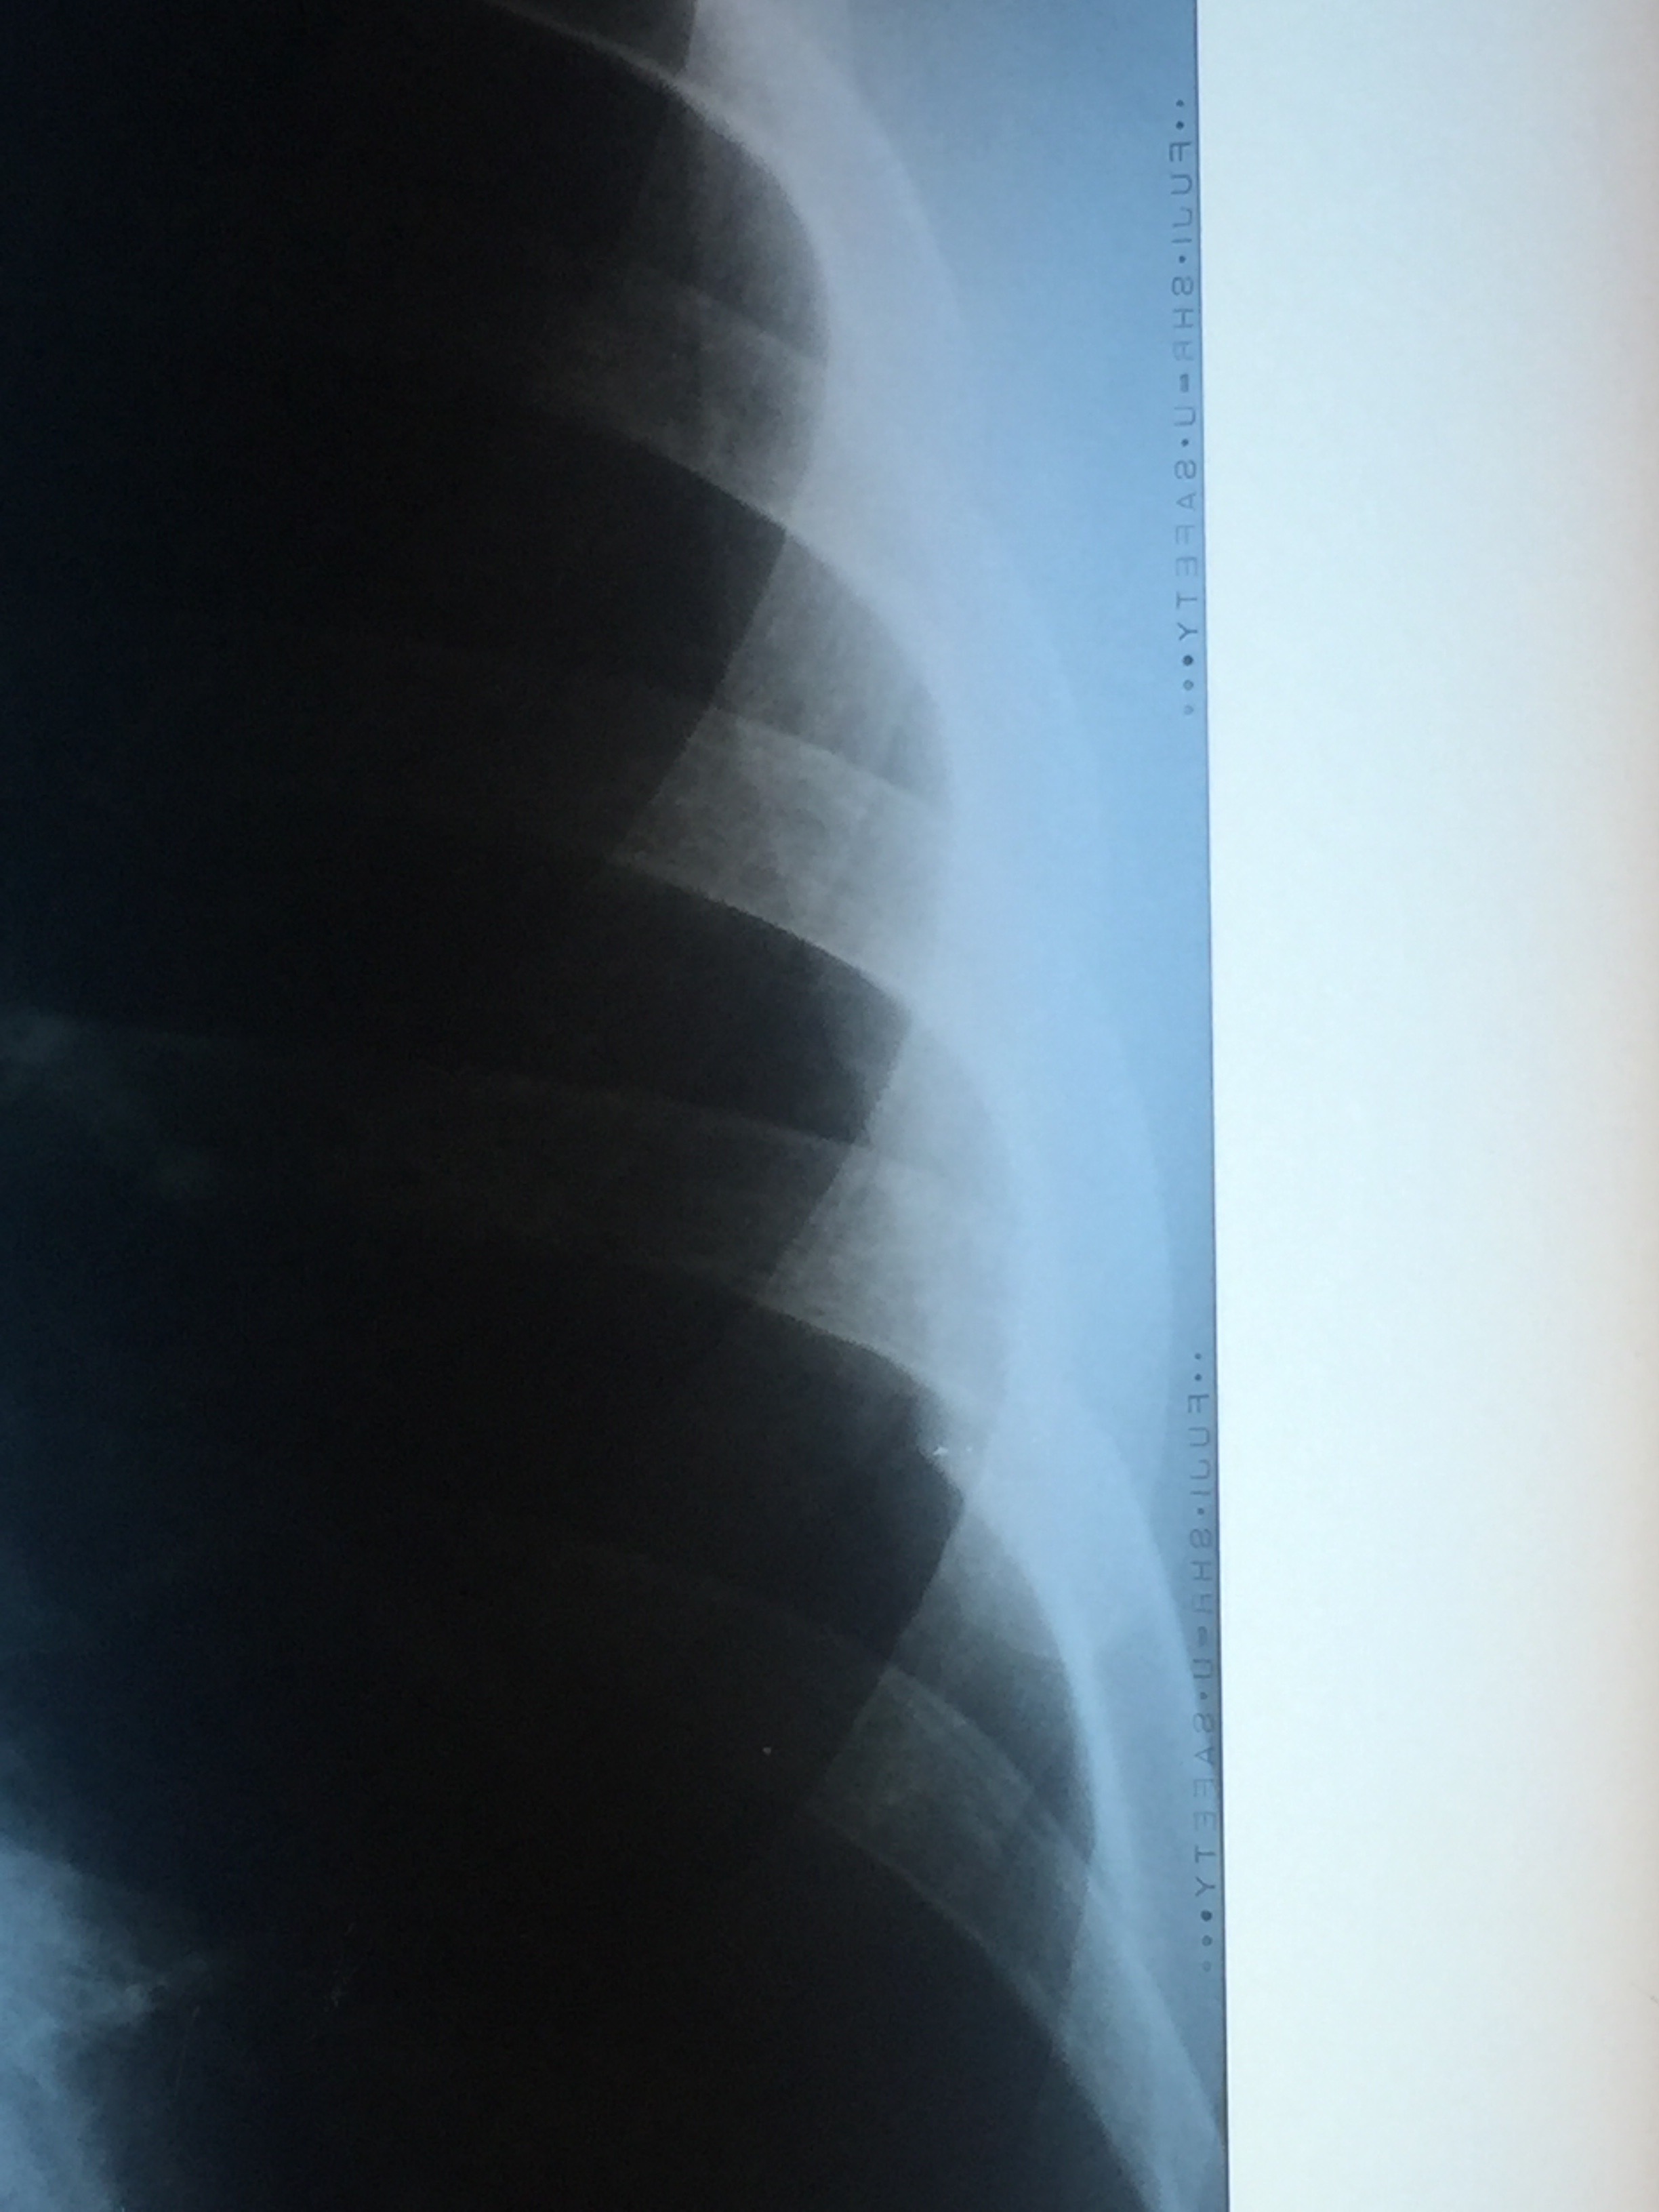

Made it to Lukla earlier today and headed straight to the hospital where an X-ray confirmed I have fractured my L7 rib from coughing these last few weeks.

The doctor has prescribed painkillers, plenty of rest, food, liquids and lots of the thick, oxygenated air available down here. He said that technically there’s nothing to prevent me going back up the mountain from a mechanical perspective – it will all be down to if I can manage the pain if I attempt to climb with the broken rib.